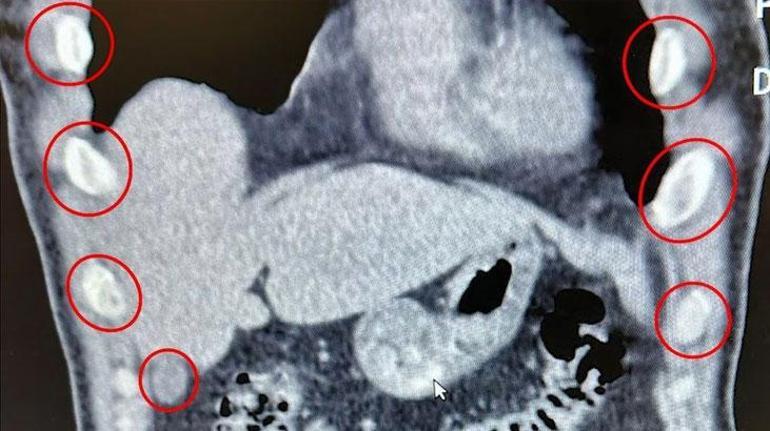

Bitlis İl Emniyet Müdürlüğü Narkotik Suçlarla Mücadele Şube Müdürlüğü ekipleri, uyuşturucu ile mücadele kapsamında önemli bir operasyona imza attı. Tatvan ilçesinde durdurulan bir otobüste yolcu olarak seyahat eden yabancı uyruklu 2 kişi gözaltına alındı. Şahısların yapılan tıbbi müdahalesinde, yuttukları 136 kapsül halinde toplam 1 kilo 48 gram metamfetamin ele geçirildi.